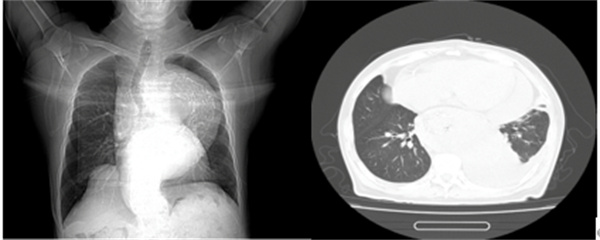

图表2 一位尚未透析的终末期肾脏病患者

也就是我们常说的“围透析期”,通常发生在刚开始透析,或者透析不充分的患者身上透析不充分,我们图中第二例患者就是一位未及时开始透析的终末期透析患者。如果透析次数不够、时间不足,毒素清除得不够理想,依然会持续刺激心包。